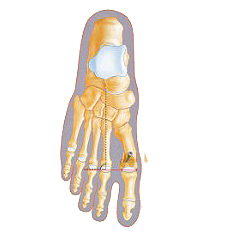

L'intervention

- De 45 mn à 1h30 d'intervention en moyenne

- Anesthésie locorégionale (le pied est endormi)

- Chirurgie ambulatoire (entrée le matin et sortie l’après-midi) ou classique (48h)

- Fragments osseux libérés et repositionnés avec vis, agrafes, voire broches parfois

- Mise en place d'un traitement de la douleur, surveillé et adapté de manière très rapprochée dans la période post-opératoire

- Pose d'une chaussure spéciale avec appui talon les jours suivants.